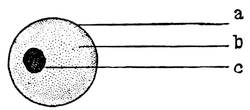

The Wolffian body, or mesonephros, appears in the shape of two longitudinal protuberances on either side of the mesentary along the spinal column. The protuberances consist of a series of transverse excretory tubules or nephrides. These tubules open into two pronephric ducts, or Wolffian ducts, which are running alongside the abdominal aorta. These two Wolffian or primitive male ducts open at the caudal end of the embryo into the hind-end of the alimentary canal, or the cloaca (Cut III, Fig. 2).

When the Wolffian body has almost reached its greatest development a second longitudinal duct makes its appearance by the evagination of the ventral surface of the Wolffian body. These ducts lie in close proximity of the Wolffian ducts, along the dorsal aspect of the coelom, or body-cavity, and are known as the ducts of Müller, or the primitive female ducts. The function of these canals in lowly organized animals is that of receiving21 from the body-cavity the ova and of evacuating them from22 the body. The Müllerian ducts also open into the cloaca. At the lower end the Müllerian and Wolffian ducts run in close apposition and form the genital cord. At this stage of development the embryo is thus hermaphroditic like the worms.